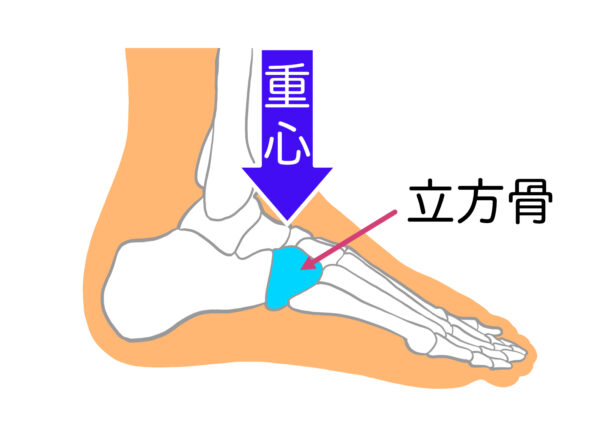

その答えが、「立方骨(りっぽうこつ)」の真下です。

立方骨とは、足の裏の外側、かかとの少し前に位置する小さな骨。

実はここが、人間が最もバランスよく立ち、歩ける“理想の重心ポイント”とされています。

■ なぜ立方骨に重心を乗せることが大事なのか?

立方骨に重心がのっていると、

・足裏のアーチが自然に働く

・本来の衝撃吸収が機能する

・下半身から上半身まで姿勢が整いやすくなる

といったメリットが生まれます。

逆に、立方骨から外れた場所に体重がのると——

足の内側に偏れば偏平足や外反母趾へ、

外側に偏ればO脚・膝痛へ、

つま先側ならふくらはぎの張りや腰痛へ……

というように、身体はどこかでバランスを取ろうとして筋肉に負担がかかり、全身の不調へつながります。

つまり、重心が立方骨にのっているかどうかは、健康な歩行・姿勢の基盤をつくるうえで非常に重要なのです。